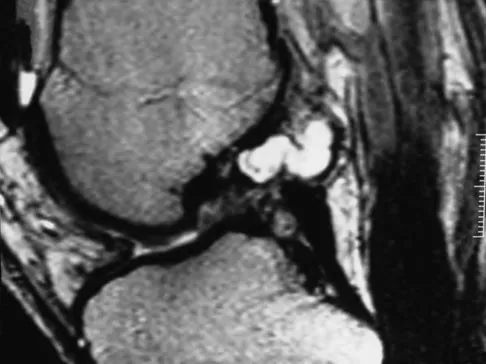

Figures 31a and 31b show the T1- and T2-weighted MRI scans of a patient's knee joint. What is the most likely diagnosis?

Explanation